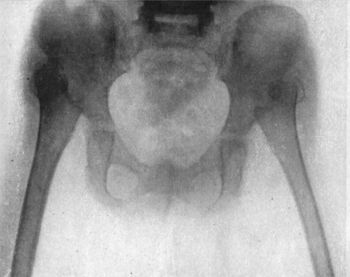

| 128. | Radiogram of Double Congenital Dislocation of Hip in a Girl | 249 |

| 129. | Innominate Bone and Upper End of Femur from a case of Congenital Dislocation of Hip | 250 |

| 130. | Congenital Dislocation of Left Hip in a Girl | 251 |